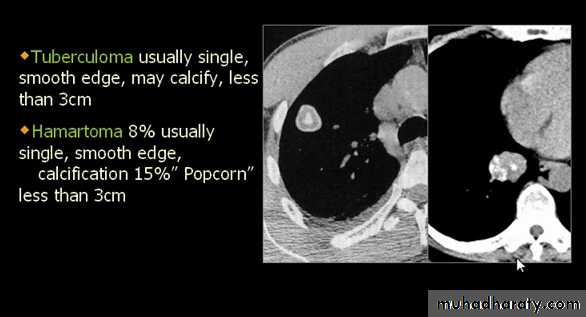

Tuberculoma